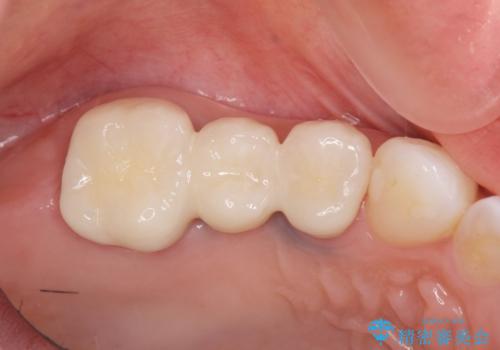

- 39.6万円(ジルコニアクラウン×3・仮歯×3)費用は治療当時の料金となります

ジルコニアブリッジは、インプラントと違い手術の必要がなく審美的に咬合機能の回復ができる補綴手段です。